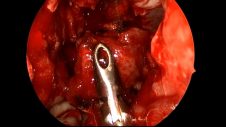

Hemangiopericytoma Resection Part 1 of 2

Hemangiopericytoma Resection Part 2 of 2